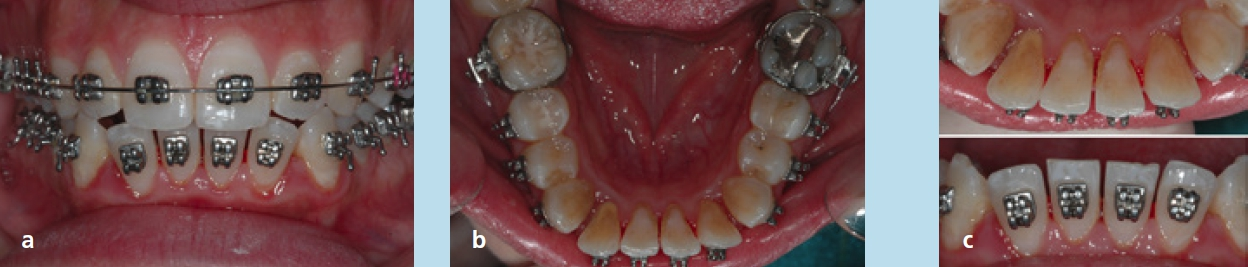

Die Patientin stellte sich im Alter von 23 Jahren zu einer kieferorthopädischen Beratung vor. Sie störten die Engstände im Unterkieferzahnbogen. Die extraoralen Aufnahmen zeigen ein schönes, harmonisches, leicht konvexes Profil, das nach den Grundregeln der Ästhetik nicht verändert werden darf (Abb. 18a bis c). Die intraoralen Aufnahmen zeigten zu Behandlungsbeginn eine Angle-Klasse-I-Okklusion, Tendenz zu Klasse III rechts und Klasse I links. Auf der Frontalaufnahme ist die knappe sagittale und vertikale Frontzahnstufe zu sehen (Abb. 19a bis c). Im Rahmen der Modellanalyse konnte eine harmonische Breitenrelation beider Zahnbögen im Bereich der Molaren und Prämolaren ermittelt werden, im Oberkiefer waren die Platzverhältnisse ausgeglichen. Im Unterkiefer lag ein Engstand von insgesamt 5 mm vor, wobei sich die Engstände auf die Frontzahnregion konzentrierten (Abb. 19d und e). Das angefertigte OPG (Abb. 20) zeigte, dass alle Zähne vorhanden und die Zähne 38 und 48 retiniert und verlagert waren. Im Seitenzahngebiet war eine konservierende Versorgung zu verzeichnen. Die parodontale Situation war röntgenologisch sowie klinisch unauffällig und die Knochenverhältnisse ließen eine orthodontische Behandlung zu. Die Fernröntgenaufnahme (Abb. 21) zeigte keine skelettalen Auffälligkeiten. Die Oberkieferfront stand nahezu achsengerecht, die Unterkieferfront war nach labial gekippt (Tab. 3).

Für die Behandlung und geplanten Zahnbewegungen wurde eine festsitzende Apparatur (0,022 × 0,028 Slot-Brackets) eingegliedert; im Oberkiefer erfolgte eine vollständige Bebänderung, im Unterkiefer nur eine Teilbebänderung der Seitenzähne (Abb. 22a bis c). Aufgrund der Achsenstellung der Fronten im Unterkiefer sollte eine weitere labiale Kippung bei der Auflösung des Engstandes vermieden werden. Um dies weitestgehend umsetzen zu können, wurde im gesamten Frontzahngebiet und bei den seitlichen Zähnen inklusive der Mesialfläche der Unterkiefereckzähne um insgesamt 4 mm gestrippt (0,20 bis 0,25 je Approximalfläche). Die Form der Zähne und der Verlauf der Gingiva ließen dies zu. Zu Beginn der Behandlung wurden nur die 1. Molaren, Prämolaren und Eckzähne bebändert, um die Proklination der unteren Schneidezähne zu vermeiden. Die Prämolaren wurden jeweils von mesial und distal sowie die Eckzähne von distal mit dem oszillierenden EVA-Winkelstück mit Hubbewegung gestrippt. Für eine effektive Distalisation und Ausnutzung des gewonnenen Platzes wurde in den Bogen zwischen den Zähnen 33 und 43 eine Druckfeder eingesetzt (Abb. 23). Nach vollständiger Distalisation der seitlichen Zähne wurden die Schneidezähne beklebt. Vor dem Einligieren des Bogens wurde die Unterkieferfront von mesial und distal einschließlich der mesialen Fläche der Eckzähne gestrippt. Es wurden Lace-backs und voller Bogen eingesetzt (Abb. 24a bis c).

Um die Okklusion in der vertikalen Dimension zu kontrollieren und den knappen Überbiss nicht zu verlieren, wurden zwischen den oberen Eckzähnen einerseits und den unteren Eckzähnen sowie 1. Prämolaren andererseits up & down-elastics in Form eines Dreiecks eingehängt. In den später eingegliederten Stahlbogen wurde zudem eine entsprechende Extrusionsstufe für die Oberkieferfront eingearbeitet. Die Zahnbögen waren lückenlos ausgeformt und nivelliert. Im Seitenzahngebiet war die Okklusion auf Klasse I eingestellt, die Frontzahnstufe war in sagittaler und vertikaler Richtung physiologisch (Abb. 25a bis e). Es trat keine Profilveränderung ein (Abb. 26a bis c). Die Parameter der Fernröntgenaufnahme (Tab. 3) lassen die dentalen Veränderungen erkennen; aufgrund der Zahnhartsubstanzreduktion kam es zu einer vergleichsweise geringen labialen Kippung beider Fronten. Zur Retention wurde an den Ober- und Unterkiefereckzähnen ein Retainer fixiert. Zusätzlich wurden im Ober- und Unterkiefer Retentionsplatten eingesetzt.